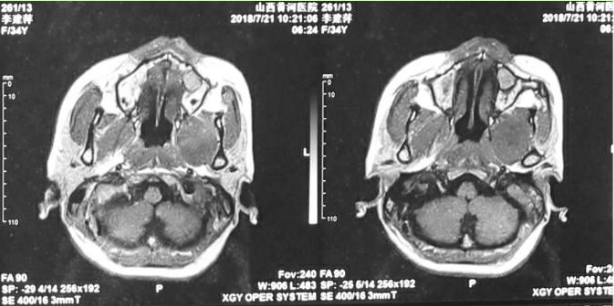

术后第一天CT显示

术前术后中颅底对比

术后增强核磁显示